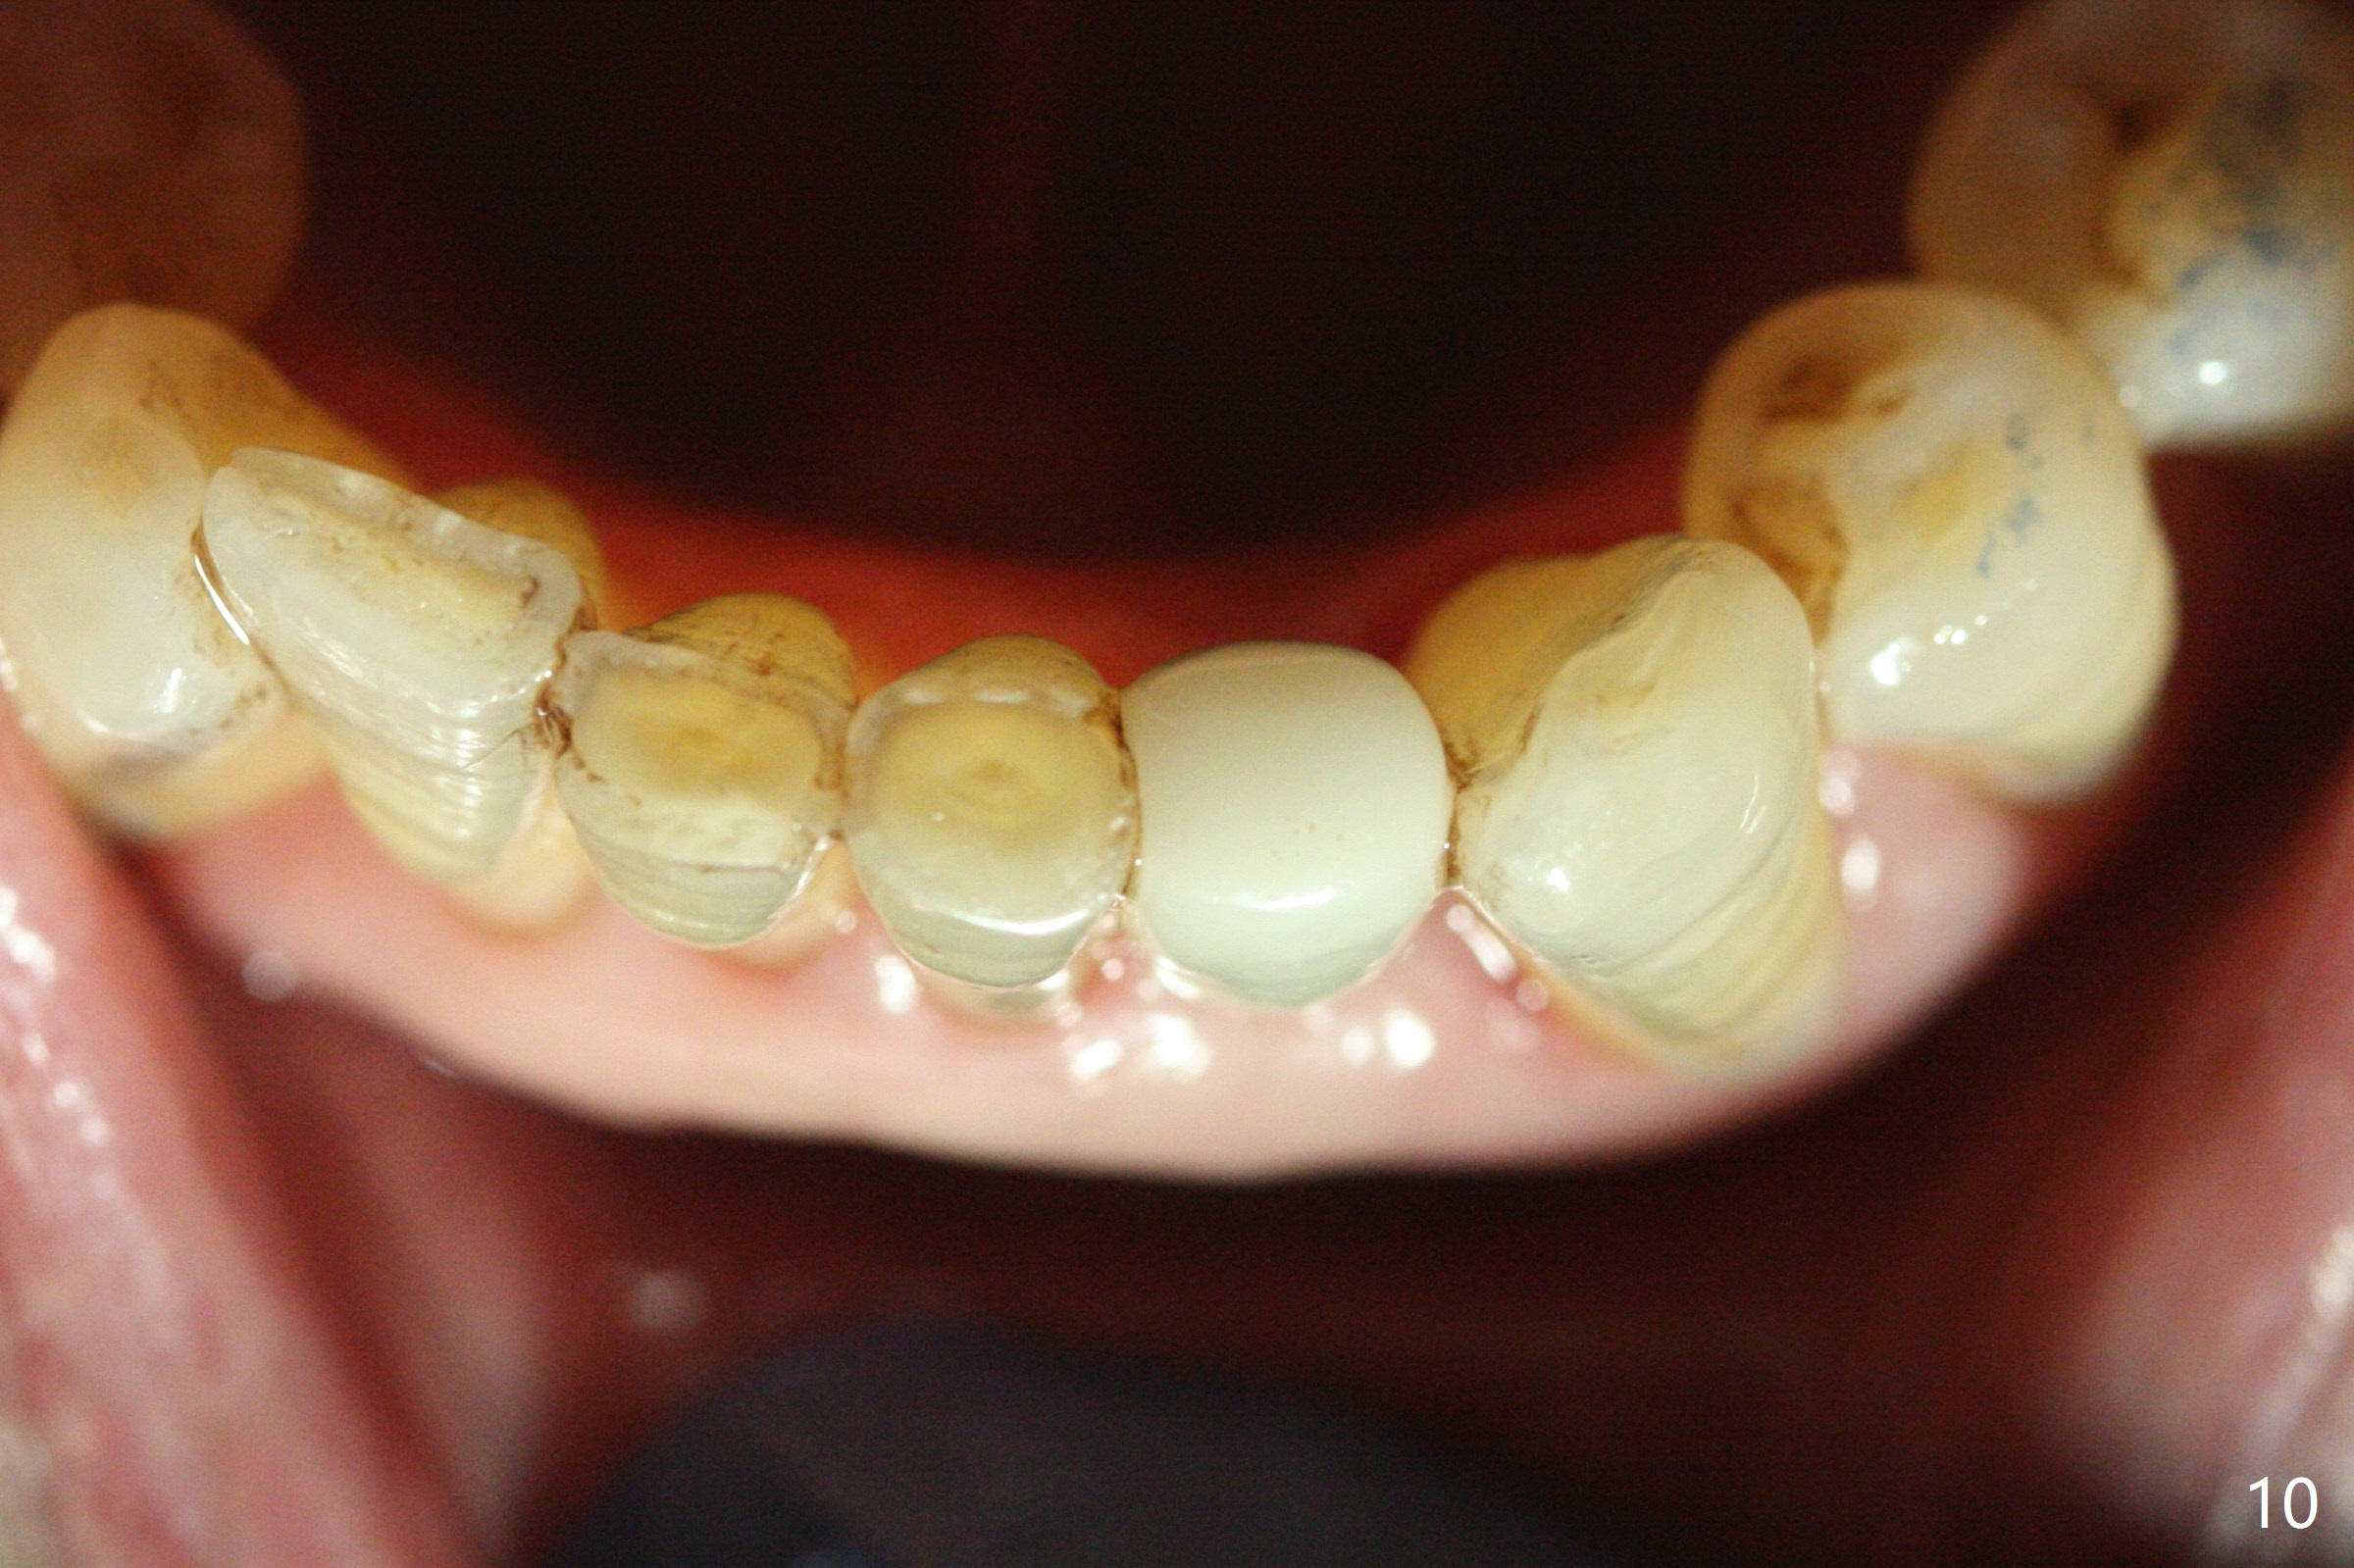

The tooth #23 is going to be extracted because the patient cannot masticate normally with mobility (Fit.1). The gingival depth is measured 2-4 mm after extraction. The 1st intraop PA taken with 1.2 mm drill for 16 mm shows the mesiodistal width is 5.11 mm (Fig.2); a 2.5x14(2) mm 1-piece implant is placed with >35 Ncm (Fig.3 with allograft placed). Following abutment preparation, an immediate provisional is fabricated to close the socket (Fig.4 P). There is no bone loss (Fig.5) or gingival inflammation (Fig.6 after reprep) 3 months postop. The narrow implant (2.5 or 2.0 mm) is indicated in the narrow edentulous space. The distal crest seems to be reduced in density and lower in height 1 year 7 months (Fig.7) and 1 year 11 months (Fig.8) post cementation. The severity does not worsen probably related to use of water pik. The crown looks bulky probably due to too large the abutment and too buccal placement of the implant (Fig.9, 10, as compared to Fig.1). A 2 mm implant may help?